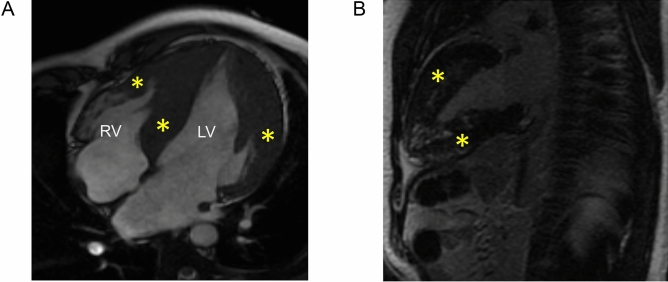

Cardiac magnetic resonance imaging

To deep phenotype the PRKAG2 cardiomyopathy patients, we performed cardiac MRI (CMR) on 8 subjects (8/22; 36% ) (AV-1, AIV-8, AIV-11, AV-11, BIV-2, CIII-5, CIV-1 and CIV-2) across three families. The studies showed diffuse and severe concentric LVH and right ventricular hypertrophy in the severely affected patients. Quantification of late gadolinium enhancement (LGE) in patients CIII-5 and BIV-2 were 10% and 9.7% respectively (Table 2). The remaining 6 patients with cardiac MRI studies did not have significant mid-myocardial or sub-endocardial enhancement on LGE studies (Fig. 3A,B). None of the patients showed LGE in the right ventricle. Cardiac MRI findings are summarized in Table 2.

Figure 3.

Cardiac MRI (SSFP Cine sequences) of patient CIII-5 showing marked hypertrophy in the region of the interventricular septum and lateral wall of the left ventricle (yellow asterisks) along with right ventricular free wall hypertrophy (red asterisk) in the apical four-chamber view (A). The two-chamber long-axis view shows patchy areas of mid-wall left ventricular late gadolinium enhancement in the anterior and inferior walls (yellow asterisks) (B).